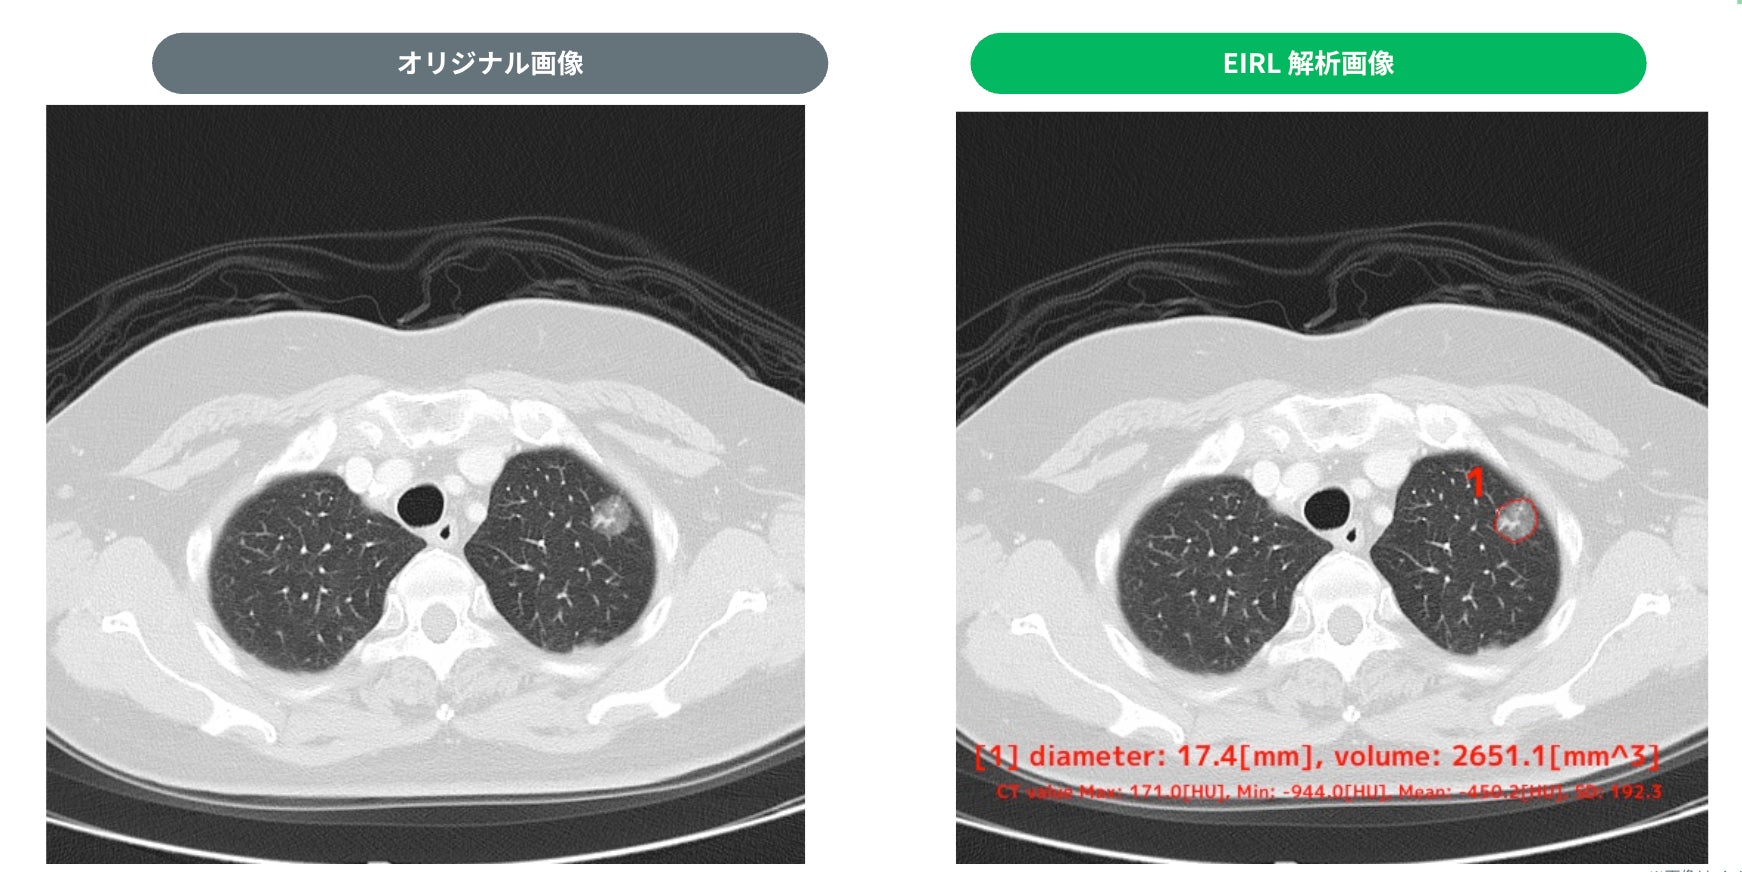

・検出例

② 17.4mm 部分充実型